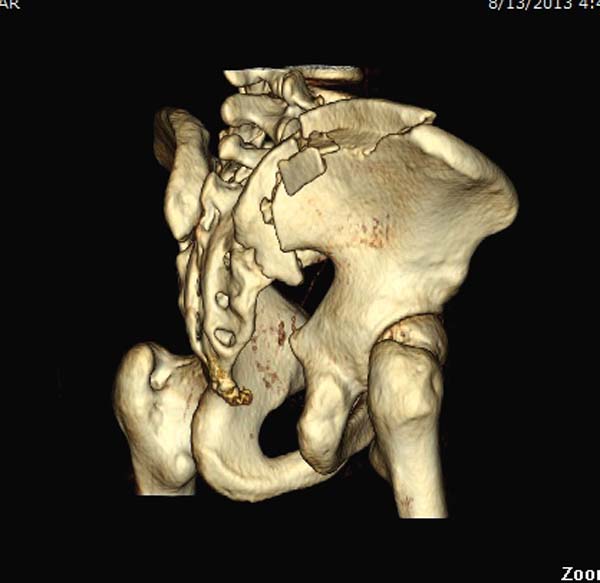

До операции желательно выставить все стандартные снимки: обзорный таза,

вход + выход. А популярный у всех 3Д используется только для общего

обзора, но не для детального изучения. Обычно КТ“для

диагностики-стандарт, а послеоперационно - дополнительный расход”. Лучше

обычные рентген-снимки, но бывают исключения, когда на снимке имеются

неясности, например, винт через сакральный форамен или через сустав!

Перелом заднего отдела крыла подвдошной кости доказывает, что задние

связочные элементы подвздошно- крестцового сочленения интактны, и такой

перелом известен как“Сrescent fracture’. Переломы разделяется на 4 типа,

и до фиксации надо хорошо изучить топографию перелома, иначе винт может

попасть в линию перелома и не удержать фиксацию.

Имя     : 5 Pelvis crush injury 3D.jpg

Тип     : image/jpeg

Размер  : 45740 байтов

Описание: отсутствует

Url     : http://weborto.net:8080/pipermail/ortho/attachments/20130827/bd348a69/attachment-0016.jpg

Вложение не в текстовом формате было извлечено…

Имя     : 7 Pelvis crush injury 3D.jpg

Размер  : 48229 байтов

Url     : http://weborto.net:8080/pipermail/ortho/attachments/20130827/bd348a69/attachment-0017.jpg